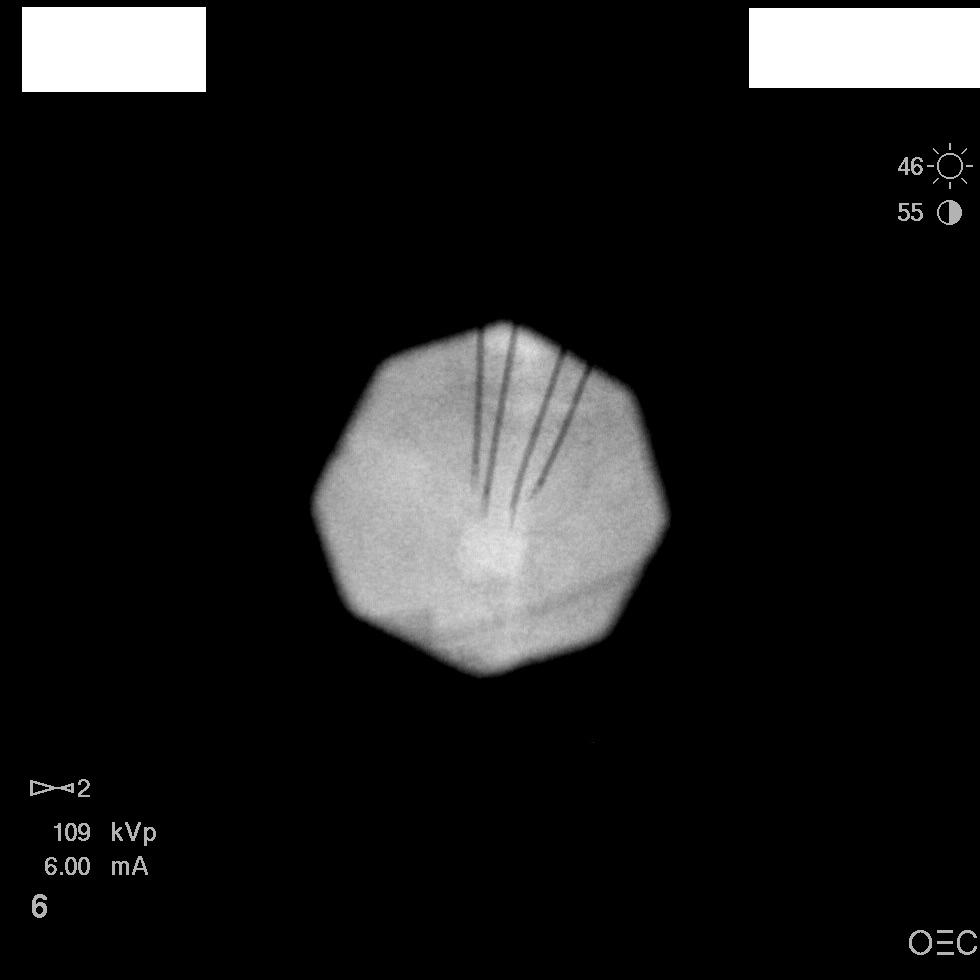

I have a patient with several months of coccyx pain. Worse with sitting, TTP over coccyx. Otherwise normal exam. No trauma, but she has an anteriorly displaced coccyx. Failed NSAIDs and no one around me does good pelvic floor PT. I scheduled her for ganglion impar injection, but her insurance won't pay for it. They wouldn't even let me to a peer-to-peer... they just straight up said they won't cover it. Any other treatment options? I don't want to send her to a surgeon. Thanks.